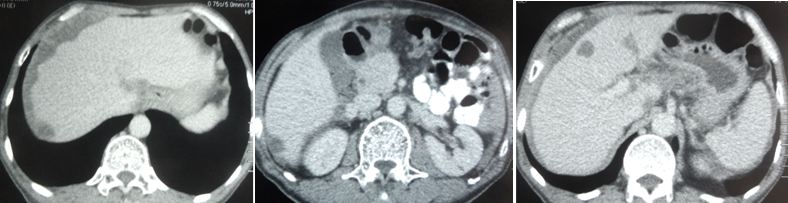

Salah satu dari dua kelenjar getah bening dipengaruhi kanker. CT scan pada 9 Mei 2018, menunjukkan kanker telah menyebar ke hatinya.

CT scan pada 5 September 2018 menunjukkan bahwa tumor di hatinya telah menyusut dari 2,49 cm menjadi 2,06 cm. Tapi itu tidak hilang.

CT scan pada 29 Oktober 2019 menunjukkan:

• Asites ringan di sekitar hati.

• Kista multipel di kedua lobus hati.

• Kompresi fraktur pada vertebra L4.